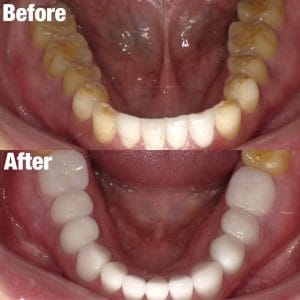

Case032

メジャーリーグでも活躍した元プロ野球選手の山口俊さんのセラミック治療を担当いたしました。

「他院で治療を受けたセラミックが欠けた」というのが主訴でしたが、よく診察するとセラミック欠けただけではなく、被せ物がしっかりと合っていないことが原因で歯茎の腫れがあり、歯石や汚れもつきやすい状態でした。また、歯列も若干歪んでいたので、この機会に全て治療いたしました。

治療後は透明感のある白さで、綺麗な歯並びになりました。また、セラミックをきちんと綺麗に削って適合よくセットしたことにより、歯茎の腫れも改善しました。

セラミックを入れた所の歯茎が腫れていて悩まれてる方はぜひご相談ください。

綺麗に削って適合よくセラミックをしてあげれば必ず改善します。